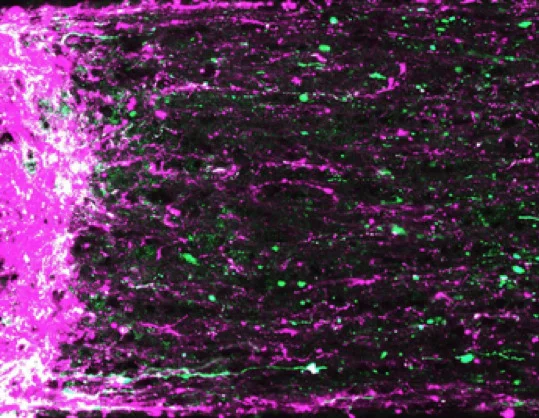

Исследователи проводили проверочные эксперименты на лабораторных крысах. После небольшой дозы анестезии животным вводили в хвостовую вену суспензию наночастиц, а потом фиксировали положение их глаза, чтобы в реальном времени отследить поведение кумарина-6 в сетчатке с помощью установки ICON (англ. In vivo Confocal Neuroimaging – прижизненная конфокальная нейровизуализация).

«Это уникальная установка, которая позволяет заглянуть в глаз живой крысе, увидеть и измерить распределение модельного вещества в сетчатке и соседних сосудах«, – отмечает Светлана Гельперина. – Установка представляет собой микроскоп, оснащенный источником возбуждения и регистрации флуоресценции, и специальные фокусирующие механизмы. Крыса во время измерений обездвижена, в глаз периодически капают капли, чтобы он не пересыхал, а мы наблюдаем за тем, как частицы циркулируют в крови и что с ними происходит потом».

В результате ученые установили, что наночастицы остаются внутри сосудов и не проходят через барьер. Но кумарин-6, который они выделяют в сосудах, питающих сетчатку, проходит через стенки сосудов в сетчатку глаза и дальше там распространяется. По данным измерений, уже спустя 15 минут после инъекции почти весь кумарин переходит из сосудов и распределяется по сетчатке, что позволяет предположить высокую скорость действия таких препаратов при использовании не модельных, а реальных терапевтических средств в будущем.